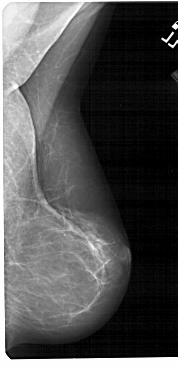

A_1524_1.LEFT_MLO

LEFT_MLO LINES 5491 PIXELS_PER_LINE 2926 BITS_PER_PIXEL 12 RESOLUTION 43.5 OVERLAY